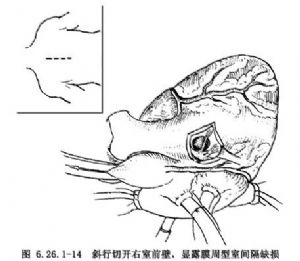

(1)切口選擇:當不需要加寬右室流出道時一般可以選用右室橫切口或斜切口,否則應選縱切口。在右心室漏斗部少血管區擬做切口部位的兩側,各做一個穿透右室壁全層的牽引縫線,切口應距左前降支8~10mm,經兩牽引線間切開右心室,用兩個小拉鉤將切口向兩側牽開,即可尋找缺損(圖16.26.1-14)。